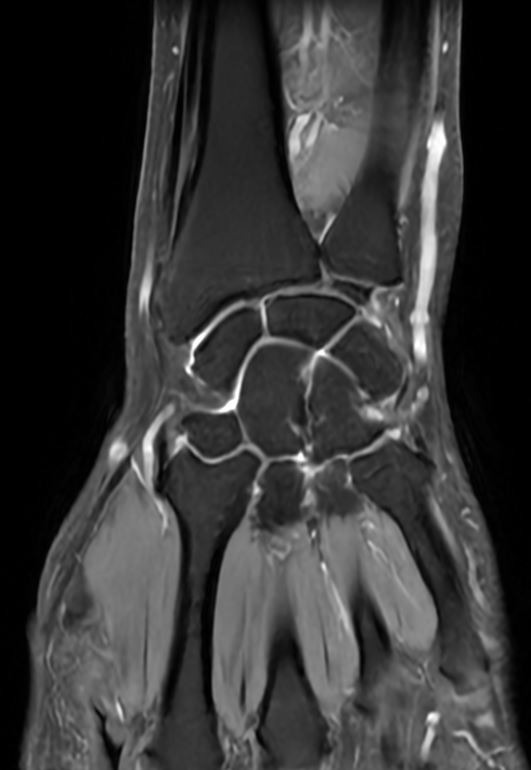

Få ekstraordinært præcise billeder af din hånd og håndled med en MR-scanning hos Progardia. Som den eneste klinik i området tilbyder vi hånd- og håndledsscanning med avanceret 3 tesla teknologi og AI-forbedret billedkvalitet. Vores erfarne specialister sikrer dig præcis diagnosticering af ledbånd, sener og håndrodsknogler samt tryghed gennem hele forløbet.

En MR-scanning af hånd eller håndled er en avanceret billeddiagnostisk undersøgelse, der giver detaljerede billeder af kroppens bløddele som muskler, sener, ledbånd, brusk og knogler uden brug af røntgenstråling. Vores 3 tesla MR-scanner skaber ekstremt præcise billeder ved hjælp af et kraftigt magnetfelt, der er ca. 60.000 gange stærkere end jordens magnetfelt.

Eksempler på MR Scanninger